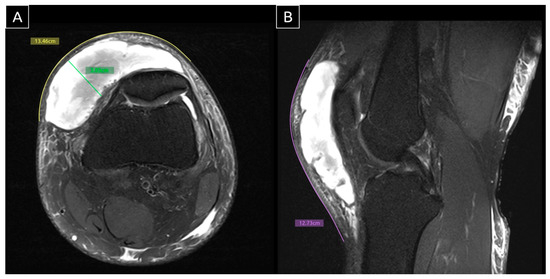

Figure 3. Axial (A) and sagittal (B) MRI. MRI was performed 11 days after the initial ultrasound scan, with measurements obtained using Horos software for skin-level tracing. The findings were consistent with the prior ultrasound, revealing a large MLL in the knee. The lesion measured 12.73 cm craniocaudally, 13.46 cm mediolaterally, and 3.00 cm in depth at its thickest region—compatible with a Type II MLL based on a history of trauma, characteristic clinical signs, and imaging evidence [3]. The MLL is a closed degloving injury resulting from shearing forces on soft tissues. These forces cause differential tissue sliding and rupture of perforating vessels, leading to bleeding and the formation of a fluid-filled cavity [4]. This cavity is typically filled with blood, lymph, and necrotic fat. If untreated, the inflammatory reaction leads to the formation of a pseudo-capsule, which prevents fluid reabsorption and results in persistent fluid accumulation [5]. This process can result in a chronic MLL, which may persist for months or even years.